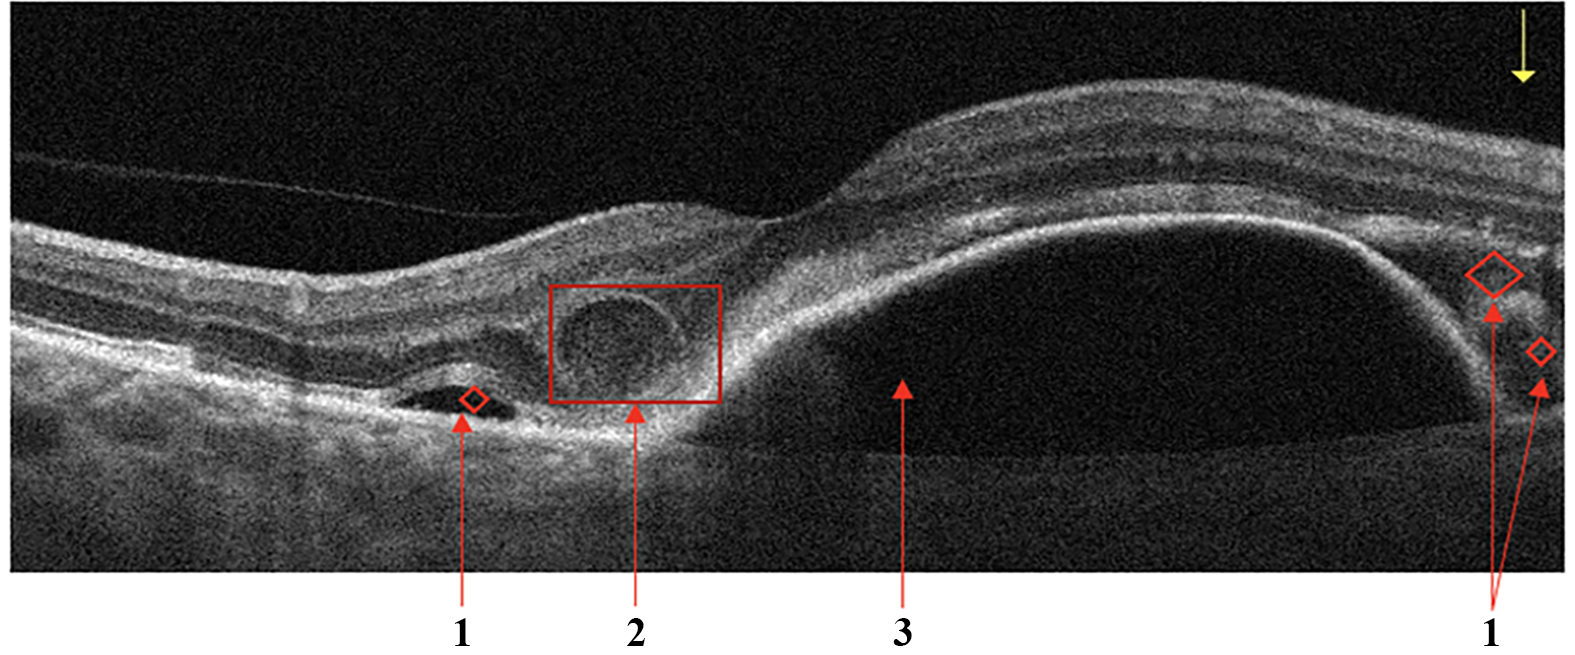

Retinal Vein Occlusion

Secondary ME is the leading cause of visual loss in patients with central retinal vein occlusion (CRVO). OCT is the critical imaging modality to diagnose and formulate a treatment plan for cystic macular edema (CME) of this etiology. In contrast to DME, the ME secondary to a branch or CRVO is generally cystic and localized to the inner retina following leakage from engorged veins, Fig.5a. OCT scans also show a higher level of hyperreflectivity of the inner retina due to ischemia. The long-term prognosis of vein occlusion will depend on the degree of ischaemic damage to the retinal tissue and the structural damage to the neural pathways after CME resorption. The presence and severity of any DRIL is an indicator of likely visual prognosis [35, 36].

Figure 5: Retinal Vein Occlusion (RVO). Cystic macular edema in central retinal vein thrombosis. (a): 1 - Intraretinal fluid (IRF), 2 - hyperreflectivity of the inner retinal layers; Signs of Retinal Artery Occlusion (RAO) (a): 1 - Increased hyperreflectivity of the inner retina following ischemia, 2 - prominent middle limiting membrane (p-MLM).

Retinal Artery Occlusion

Occlusion of the central retinal artery (CRAO) and its branches (BRAO) leads to the formation of acute tissue ischemia, giving a specific OCT picture - pronounced hyperreflectivity, loss of homogeneity, and edema of the inner parts of the retina containing the ganglion cells, Fig.5b. Also, a biomarker of acute ischemia is a prominent middle limiting membrane (p-MLM) - a hyperreflective line or band located in the inner part of the outer plexiform layer at the border with the outer nuclear layer. It is not ordinarily visible, which appears in the early period of the pathological damage and is due to opacification of the middle retinal layers [37].

Figure 6: Vitreomacular Interface Disease (VID). Vitreomacular traction syndrome (a): 1 - Posterior hyaloid membrane, 2 - Vitreomacular adhesion zone, 3 - Emerging neurosensory retinal defect; Retinal interface disorder (b): 1 - intraretinal fluid (IRF), 2 - Edges of the tear, 3 - detached posterior hyaloid membrane; Lamellar tear (c).